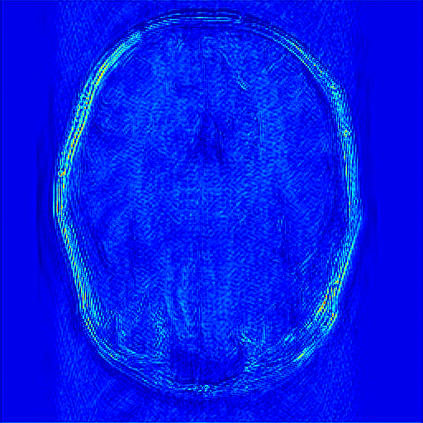

Reconstructing magnetic resonance (MR) images from undersampled data is a challenging problem due to various artifacts introduced by the under-sampling operation. Recent deep learning-based methods for MR image reconstruction usually leverage a generic auto-encoder architecture which captures low-level features at the initial layers and high?level features at the deeper layers. Such networks focus much on global features which may not be optimal to reconstruct the fully-sampled image. In this paper, we propose an Over-and-Under Complete Convolu?tional Recurrent Neural Network (OUCR), which consists of an overcomplete and an undercomplete Convolutional Recurrent Neural Network(CRNN). The overcomplete branch gives special attention in learning local structures by restraining the receptive field of the network. Combining it with the undercomplete branch leads to a network which focuses more on low-level features without losing out on the global structures. Extensive experiments on two datasets demonstrate that the proposed method achieves significant improvements over the compressed sensing and popular deep learning-based methods with less number of trainable parameters. Our code is available at https://github.com/guopengf/OUCR.